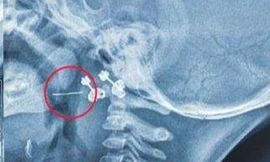

Cổ họng tôi thường khó chịu. Khi nuốt nước bọt cảm giác như có vật gì đó cản lại. Tôi thường khạc ra nhưng miếng màu trắng nhỏ và hôi. Xin hỏi bác sĩ đó là bệnh gì? Cách chữa trị ra sao? Xin cám ơn. (Vo Phuoc Binh).